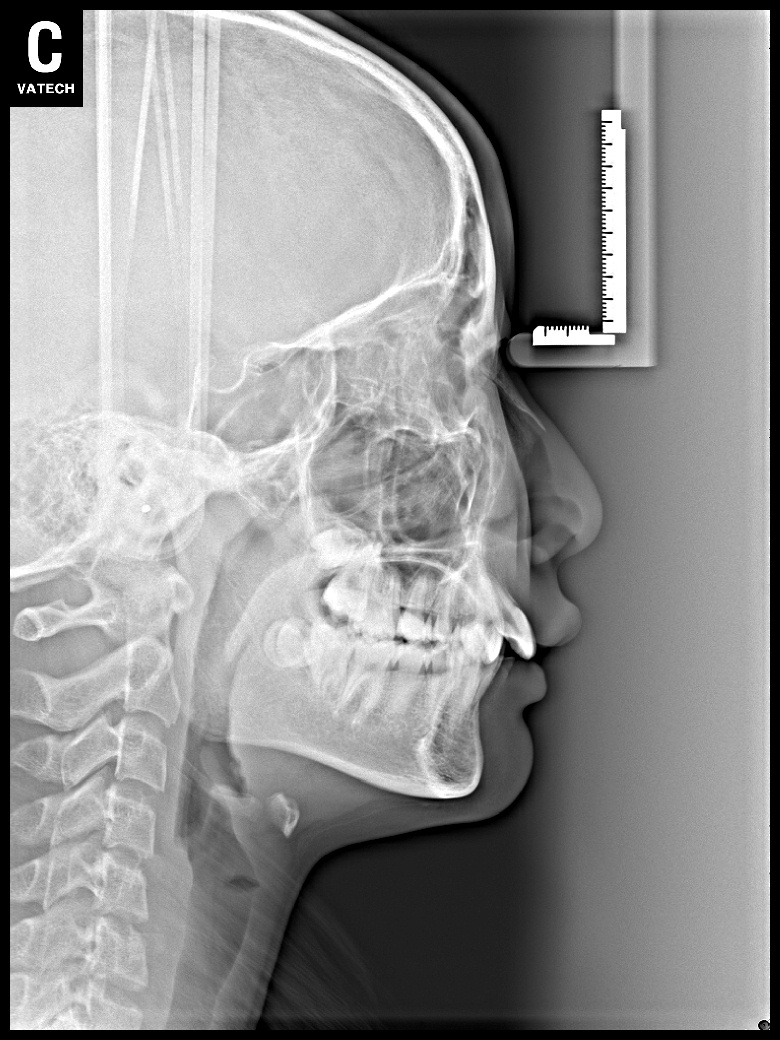

치료 전 사진입니다.